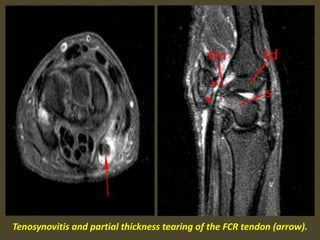

Tenosynovitis and partial thickness tearing of the FCR tendon (arrow).